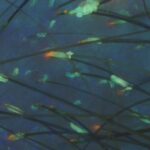

- Tricoscopía/capilografía y exámenes complementarios, si es necesario, para identificar el tipo de alopecia.

Utiliza luz LED de espectro específico para estimular el metabolismo celular, reducir la inflamación y favorecer el crecimiento de cabello más fuerte y saludable. - Tricoscopía. Examen médico no invasivo que permite observar en detalle el cuero cabelludo y los folículos pilosos mediante un dermatoscopio digital.

IMÁGENES EXAMEN CAPILAR